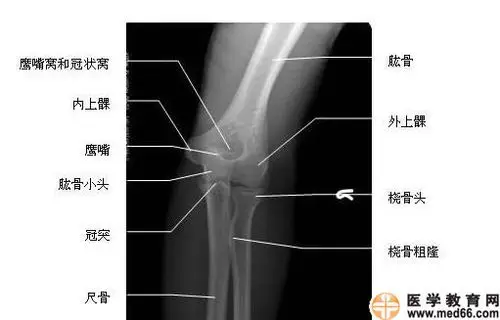

肘关节正位-x线